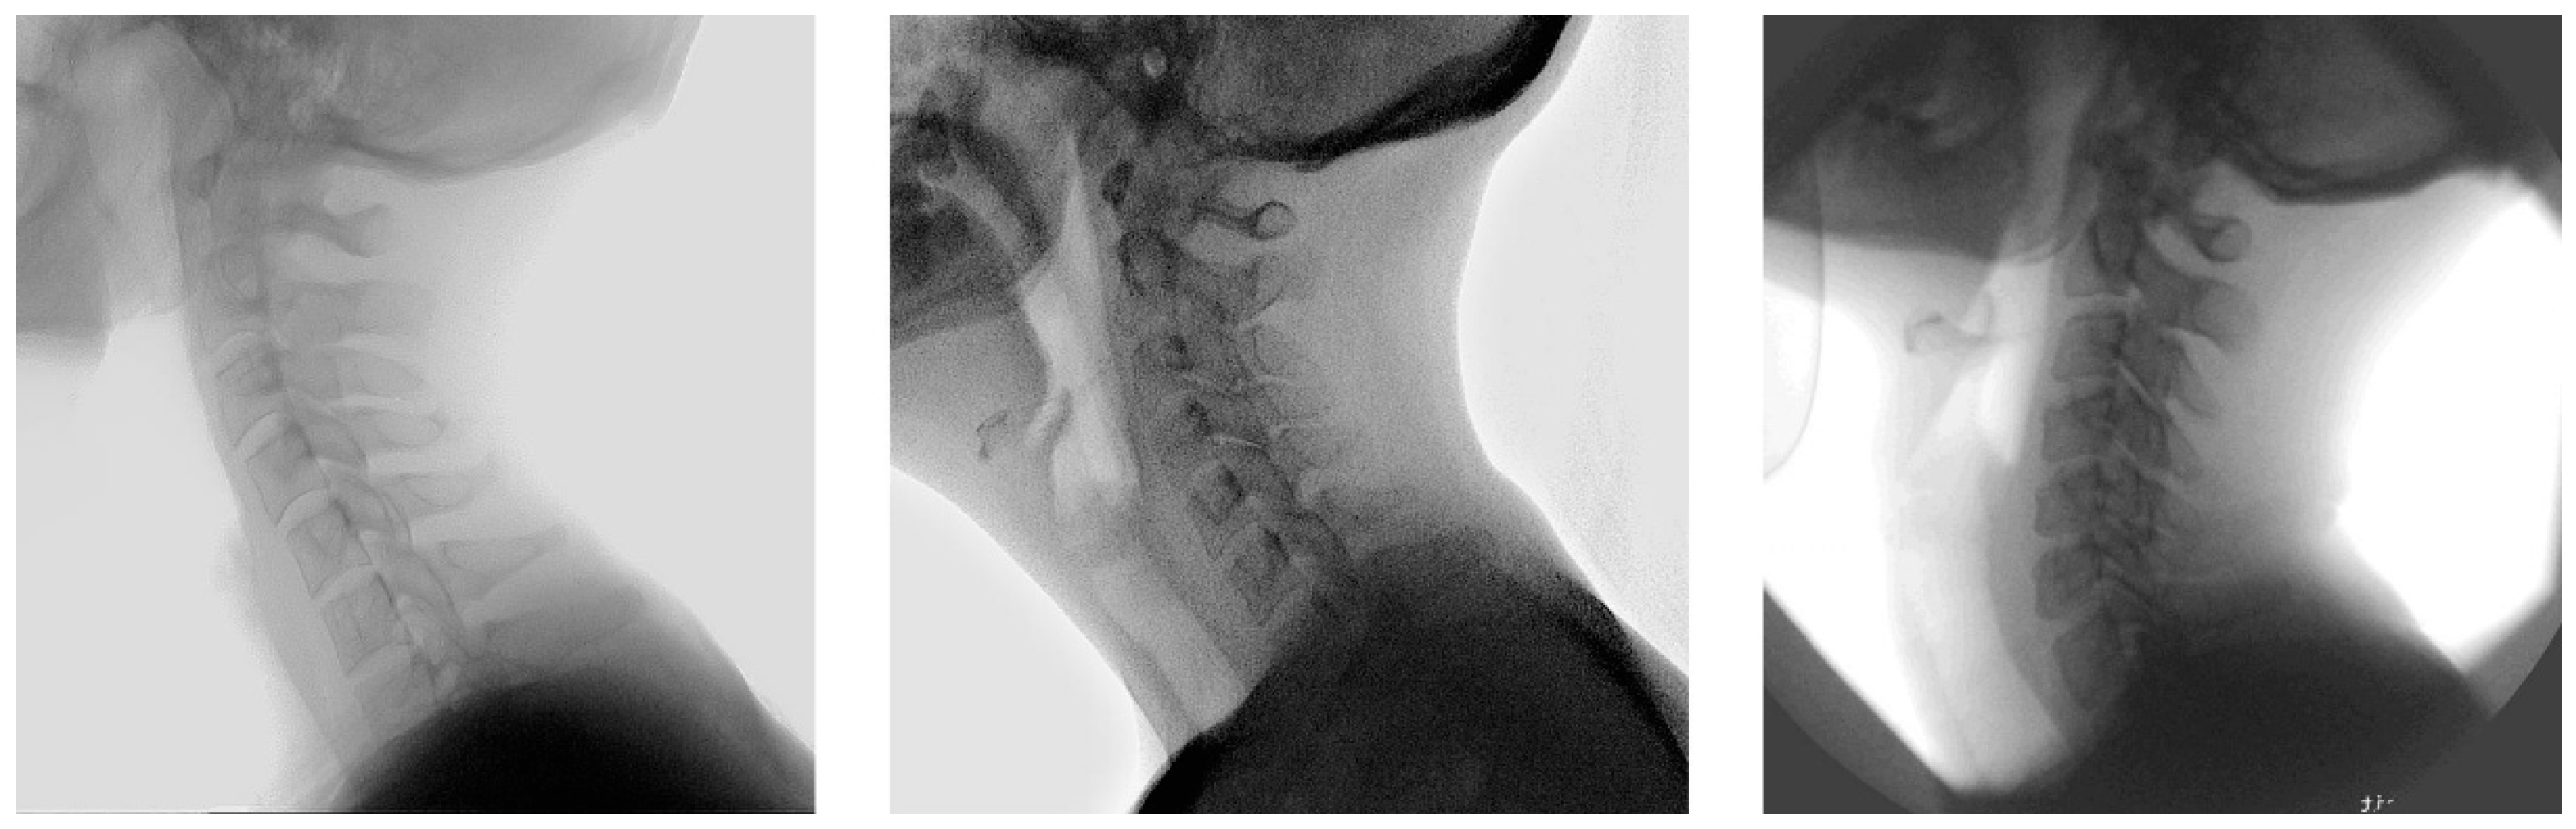

2.1. Population

2.2. Manual Annotation

2.3. Development of the Model

2.4. Dataset